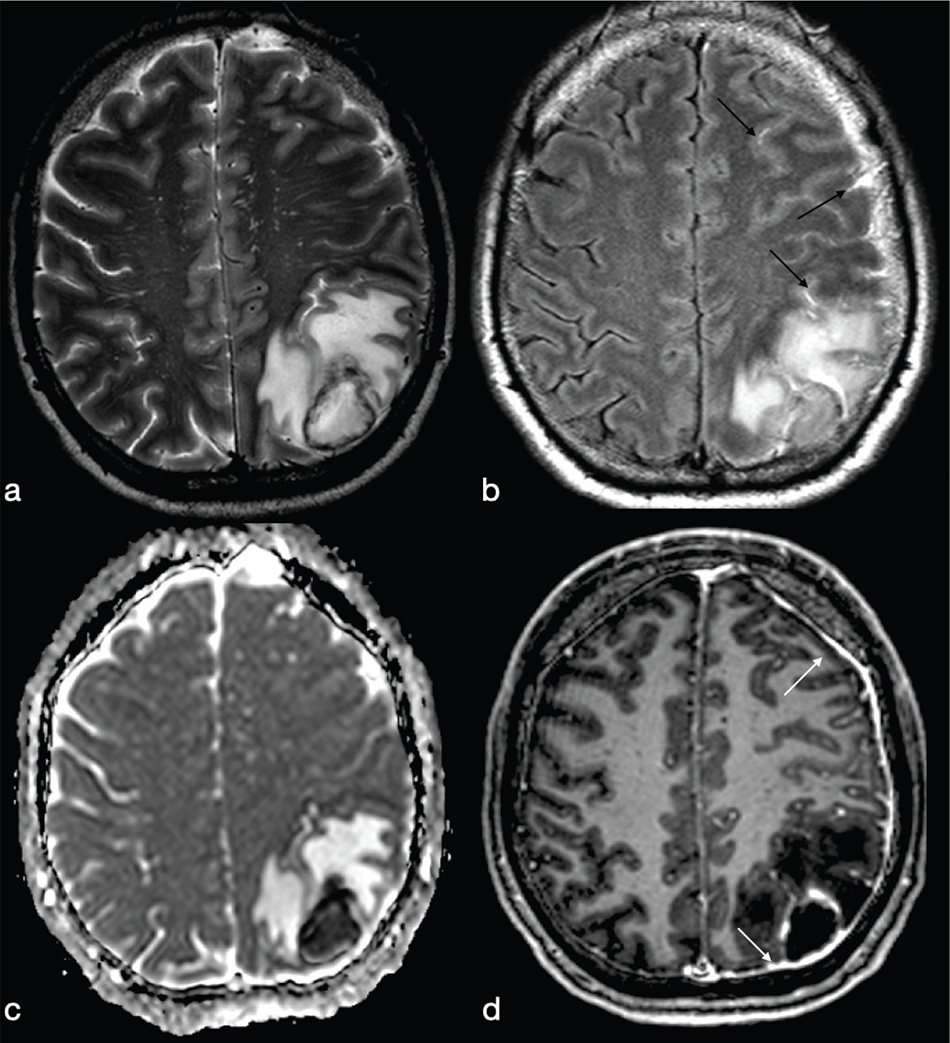

FIG 3. A 45-Year-Old Man with Pyogenic Abscess Surfacing the Left Parietal Lobe Cortex. A roundish mass with a core of necrotic-cystic degeneration (a–b) showing restricted diffusion on ADC maps (c) and diffuse surrounding vasogenic oedema (a–c) with irregular rim-enhancement (d) is shown. FLAIR-T2w (b) high signal within the subarachnoid spaces reveals rupture of abscess into the subarachnoid space (black arrows in b). Meningeal involvement is also appreciable after i.v. administration of Gd (white arrows in d).

FIG 4. A 54-Year-Old Woman with Multiple Pyogenic Abscesses Involving the Right Thalamus and Right Temporal Region. The abscesses show a thin capsule on T2w (a) binding a core of restricted diffusion (asterisk in b) with correspnding low signal in ADC maps (c). Smooth ring enhancement on gadolinium-enhanced T1w (d) is present. Satellite abscesses (black and white arrows in a and d respectively) give a polylobulated appearance.